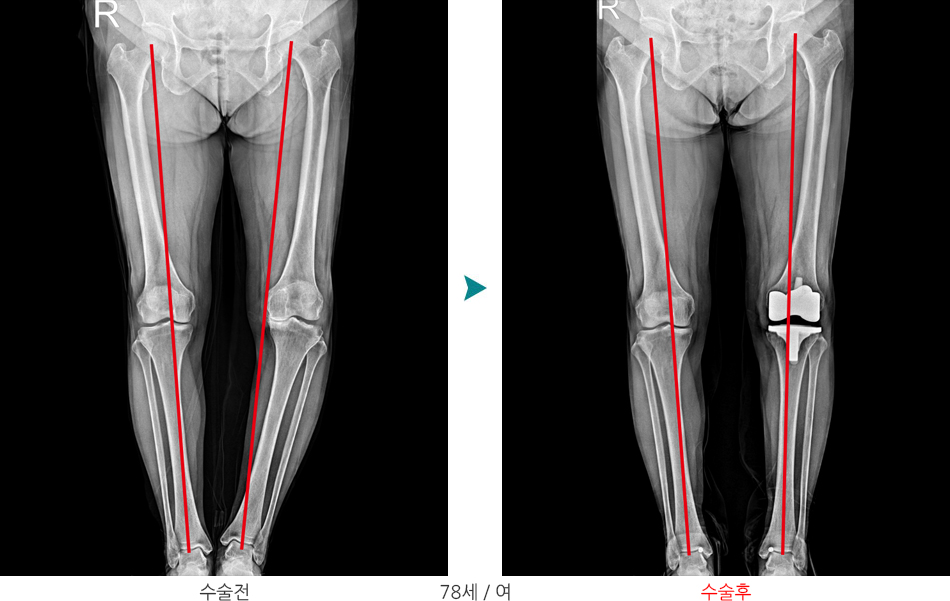

비교적 젊은 연령에서 내반 및 외반 변형이 있는 경우 경골 근위부 절골술을 시행하고 관절이 거의 닳아 없어진 고령의 환자의 경우에는 인공관절 수술을 시행합니다.

수술 후 다리 축 변화(외반변형, 외반슬)

수술 후 다리 축 변화(내반변형, 내반슬)

수술 후 다리 축 변화